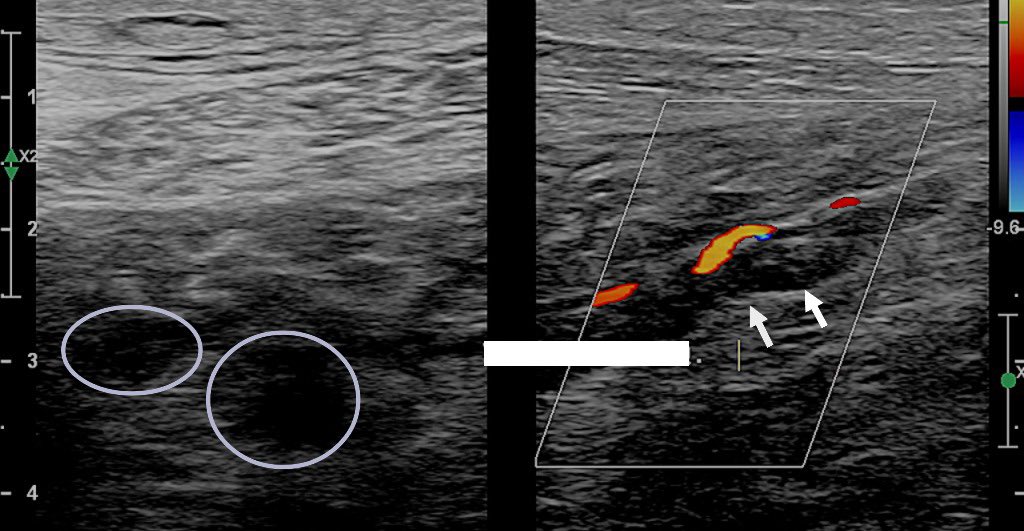

Atypical incompetent perfurating vein:

• posterior in the middle calf (21 cm from the ground).

• UIP name: intergemellar perfurating vein, 3.4.3.

share.google/rEHnAQcTG0CUvl…

#vascularultrasound